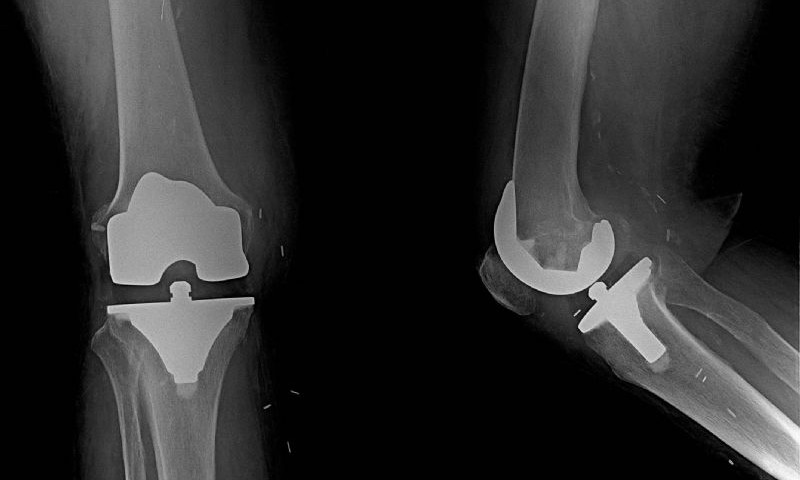

Total Diz Protezi Örnek Olgular